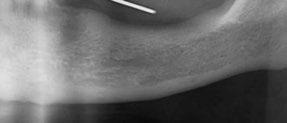

Protocolo Di2gitalArch® 2.0: Carga inmediata en el día en maxilar superior atrófico. Con Ziacom Galaxy, por el Dr. Luis Cuadrado Canals.